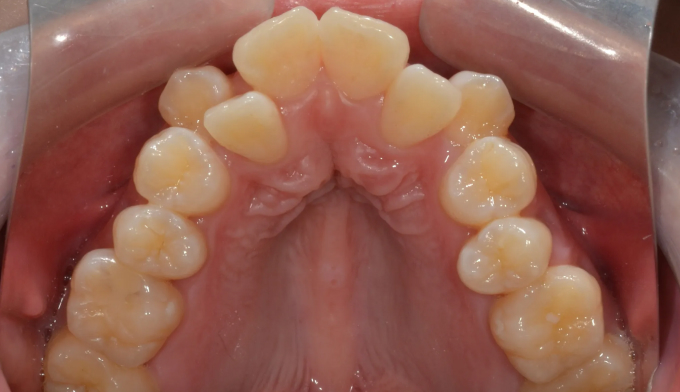

덧니를 해소하기 위해 필요한 공간의 양도 매우 많으며, 돌출의 정도도 심한편입니다. 또한 개방교합도 존재하고 있으며, 악궁의 폭도 매우 좁은편입니다.

필요한 공간의 양이 너무 많아 악궁 확장과 작은어금니 발치를 모두 시행하였습니다.